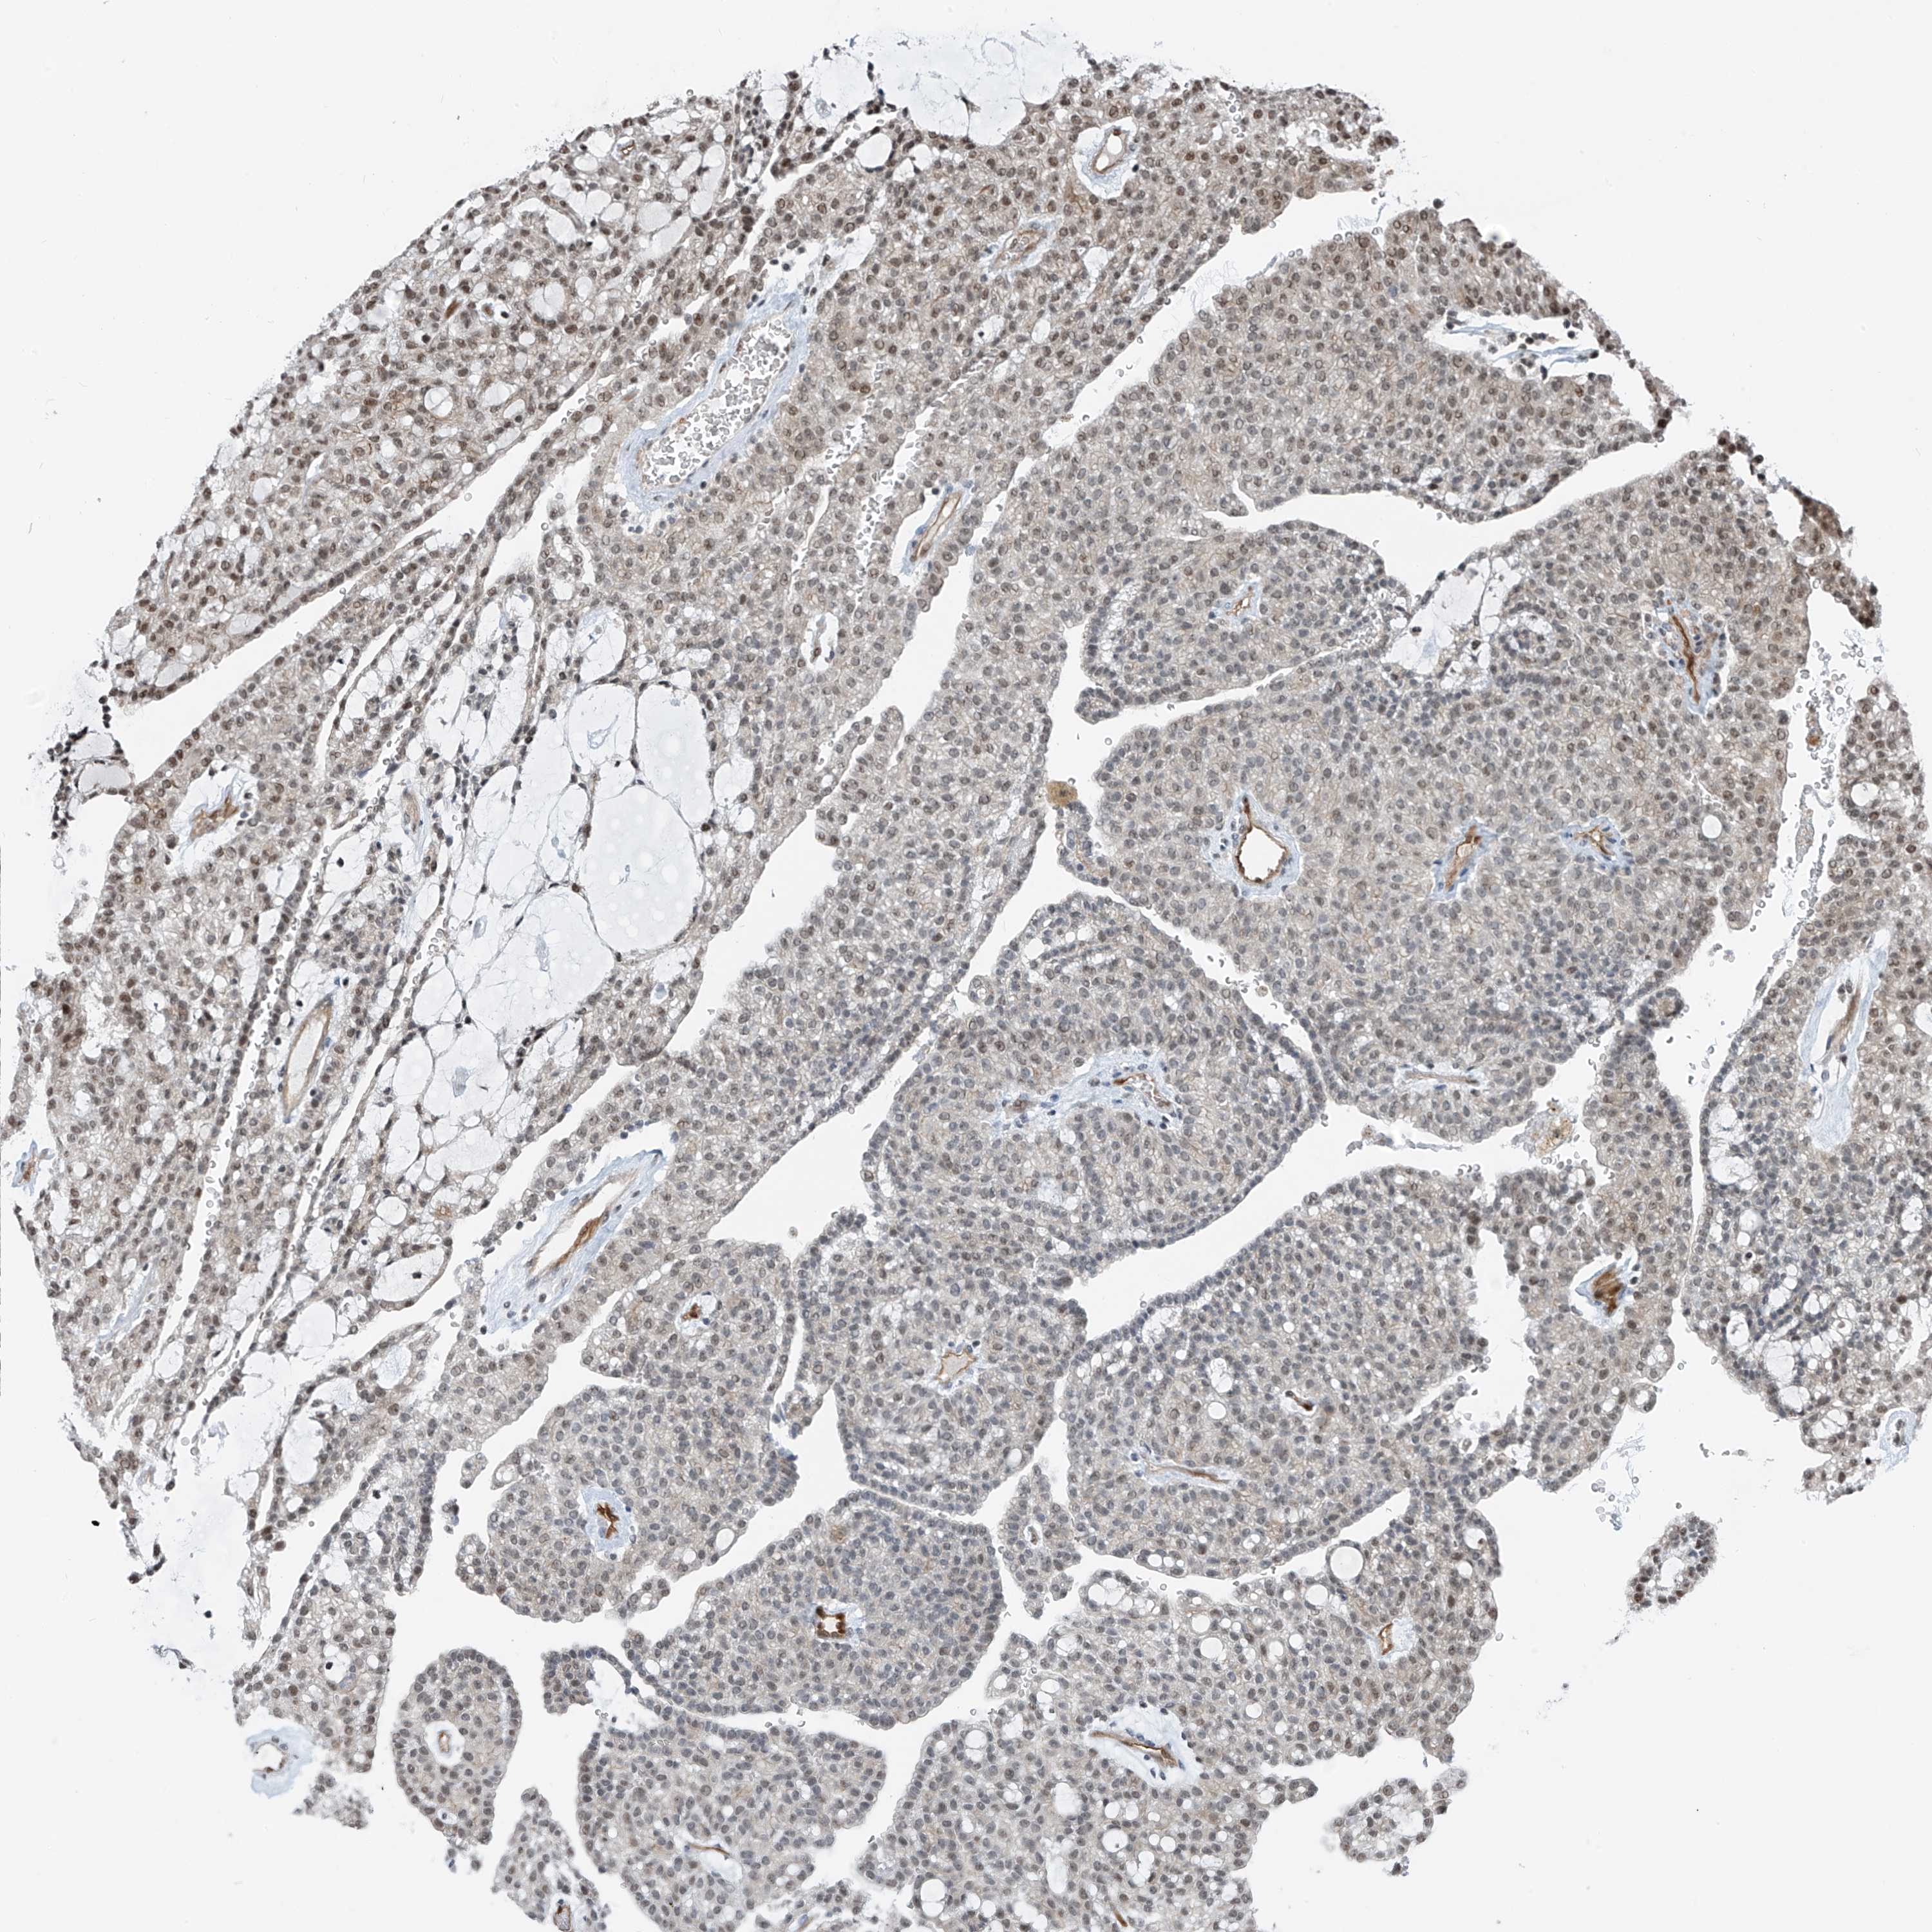

KIDNEY CHROMOPHOBE (TCGA) - Interactive survival scatter ploti

The Survival Scatter plot shows the clinical status (i.e. dead or alive) for all individuals in the patient cohort, based on the same data that underlies the corresponding Kaplan-Meier plots. Patients that are alive at last time for follow-up are shown in blue and patients who have died during the study are shown in red.

The x-axis shows the expression levels (FPKM) of the investigated gene in the tumor tissue at the time of diagnosis. The y-axis shows the follow-up time after diagnosis (years). Both axes are complimented with kernel density curves demonstrating the data density over the axes. The top density plot shows the expression levels (FPKM) distribution among dead (red) and alive patients (blue). The right density plot shows the data density of the survived years of dead patients with high and low expression levels respectively, stratified using the cutoff indicated by the vertical dashed line through the Survival Scatter plot. This cutoff is automatically defined based on the FPKM cutoff that minimizes the p-score. The cutoff can be changed by dragging the vertical line or by entering a cutoff value in the square labeled "Current cut-off".

Under the Survival Scatter plot the p-score landscape (black curve; left axis) is shown together with dead median separation (red curve; right axis). Dead median separation is the difference in median mRNA expression between patients who have died with high and low expression, respectively. It is calculated as follows: median FPKM expression of dead patients with high expression - median FPKM expression of dead patients with low expression. This is intended to aid the user in visually exploring custom cutoffs and the associated p-scores and dead median separation.

Individual patient data is displayed and can be filtered by clicking on one or more of the category buttons on the top of the page. Categories describing expression level and patient information include: high, low, alive, dead, female, male and tumor stages. The scale of the x-axis can be toggled between linear and log-scale by clicking on the "x log" button. Mouse-over function shows TCGA ID, patient information and mRNA expression (FPKM) for each patient.

& Survival analysisi

Kaplan-Meier plots summarize results from analysis of correlation between mRNA expression level and patient survival. Patients were divided based on level of expression into one of the two groups "low" (under cut off) or "high" (over cut off). X-axis shows time for survival (years) and y-axis shows the probability of survival, where 1.0 corresponds to 100 percent.

RBP7 is not prognostic in Kidney Chromophobe (TCGA)

: 31.88

Average pTPM 21.3

Number of samples 64